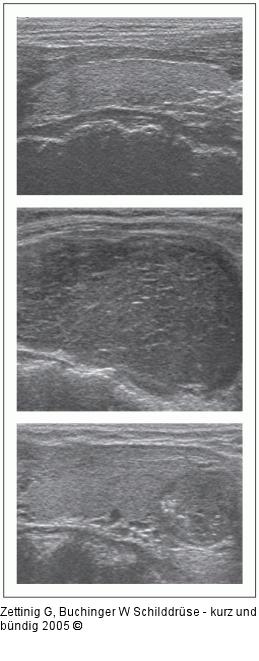

Abbildung 2: Gestörte Schilddrüsenmorphologie Gestörte Schilddrüsenmorphologie im Ultraschall (Längsschnitte): oben: normale Echostruktur; Mitte: diffus echoarmes Grundmuster, vergrößerte Schilddrüse; unten: Herdbefund: scharf und regelmäßig begrenzter echoarmer Knoten mit kleinsten Kalkeinlagerungen kaudal. |

Abbildung 2: Gestörte Schilddrüsenmorphologie

Gestörte Schilddrüsenmorphologie im Ultraschall (Längsschnitte): oben: normale Echostruktur; Mitte: diffus echoarmes Grundmuster, vergrößerte Schilddrüse; unten: Herdbefund: scharf und regelmäßig begrenzter echoarmer Knoten mit kleinsten Kalkeinlagerungen kaudal. |